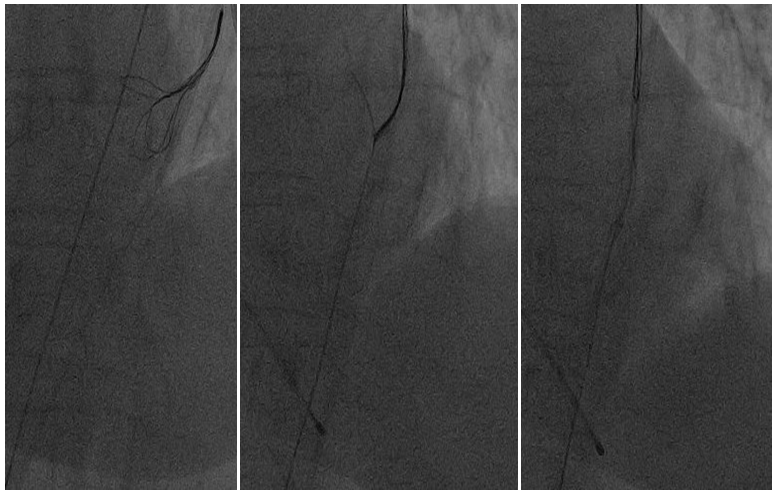

On physical examination she was symptomatic for dyspnea(NYHA class III). Midsystolic murmur was heard near midsternal border and pretibial edema was noted. Transthoracic echocardiography revealed dilatation of both atrium, left ventricular hypertropy, moderate mitral regurgitation, severe tricuspid regurgitation  and sclerosis of aortic valve with mean gradient  54 mmhg and maximal gradient 90 mmhg. Aortic valve planimetric area was calculated as 0,6 cm2. Ef:64% with pulmonary hypertension(PAPs 48 mm hg). Coronary angiography showed noncritical stenosis of coronary arteries. The decision was to perform transcatheter aortic valve implantation with transfemoral approach. A transvenous temporary pacing wire was positioned in the right ventricle via the left femoral vein. Percutaneous right femoral acces was then obtained and 18 F delivery system was used. There were extreme calcification and tortuosity in femoral and iliac arteries (Figure 1 & 2). It was very difficult to advance the delivery system. Aggressive baloon angioplasty was performed with peripheral baloons but no further advancement of the 18F system was possible. A 25 mm Amplatz Gooseneck snare was advanced from brachial artery to snare and prolapse through the sheath. This procedure allow additional tension, thereby allowing easy passage of the valve delivery system (Figure 3-5). Baloon valvuloplasty was performed before device placement, after which a 0,035 Amplatz extra stiff guidewire placed in the left ventricle. 25 mm Direct Flow Medical valve is then advanced over a stiff guidewire and deployed within the aortic annulus. Prostar were used to close the vascular access site.

Figure 3&4&5: A 25 mm Amplatz Gooseneck snare from brachial approach while capturing the wire.